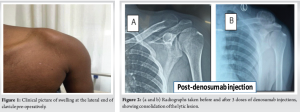

Local examination (Fig. 1):

- Single, globular swelling

- Confined to lateral 1/3rd of the clavicle measuring 7 cm × 5 cm which was fixed to the underlying bone and slightly tender on palpation

- Bony hard consistency

- The skin over the swelling was normal and pinchable

- The range of movements of the shoulder was near normal with mild painful terminal abduction

- No similar abnormal swellings were noted over the opposite shoulder and other parts of the body

- No local rise of temperature, no neurovascular deficits, and no palpable lymph nodes.

Radiologically, as in (Fig. 2a), it was thought of giant cell tumor (GCT), as it appears to be lytic lesion with internal septae and soap bubble appearance, narrow zone of transition, no periosteal reaction, eccentric lesion in a young male.

So we have a trial of denosumab injections to make it consolidate and make it easy for resection. Three doses of 60 mg subcutaneous denosumab were given at an interval of 1 month, and plain radiographs were taken before and after the injection as shown in (Fig. 2a and b).

As the lesion was consolidated with denosumab (Fig. 2b), it was diagnosed as a giant cell tumor.